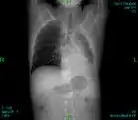

CT scan chest: Bone cancer in back and ribs, spread from lung cancer. -

X-ray: Bone cancer in hip, spread from prostate cancer. -

Bone scintigraphy: Bone cancer spread from breast cancer.